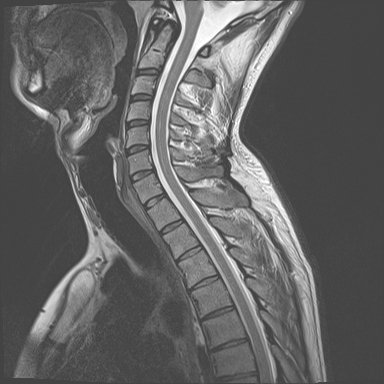

白色文字(排除指定关键词) Imaging Anatomy: interactive PACS-like atlas of radiological anatomy

解剖学模块